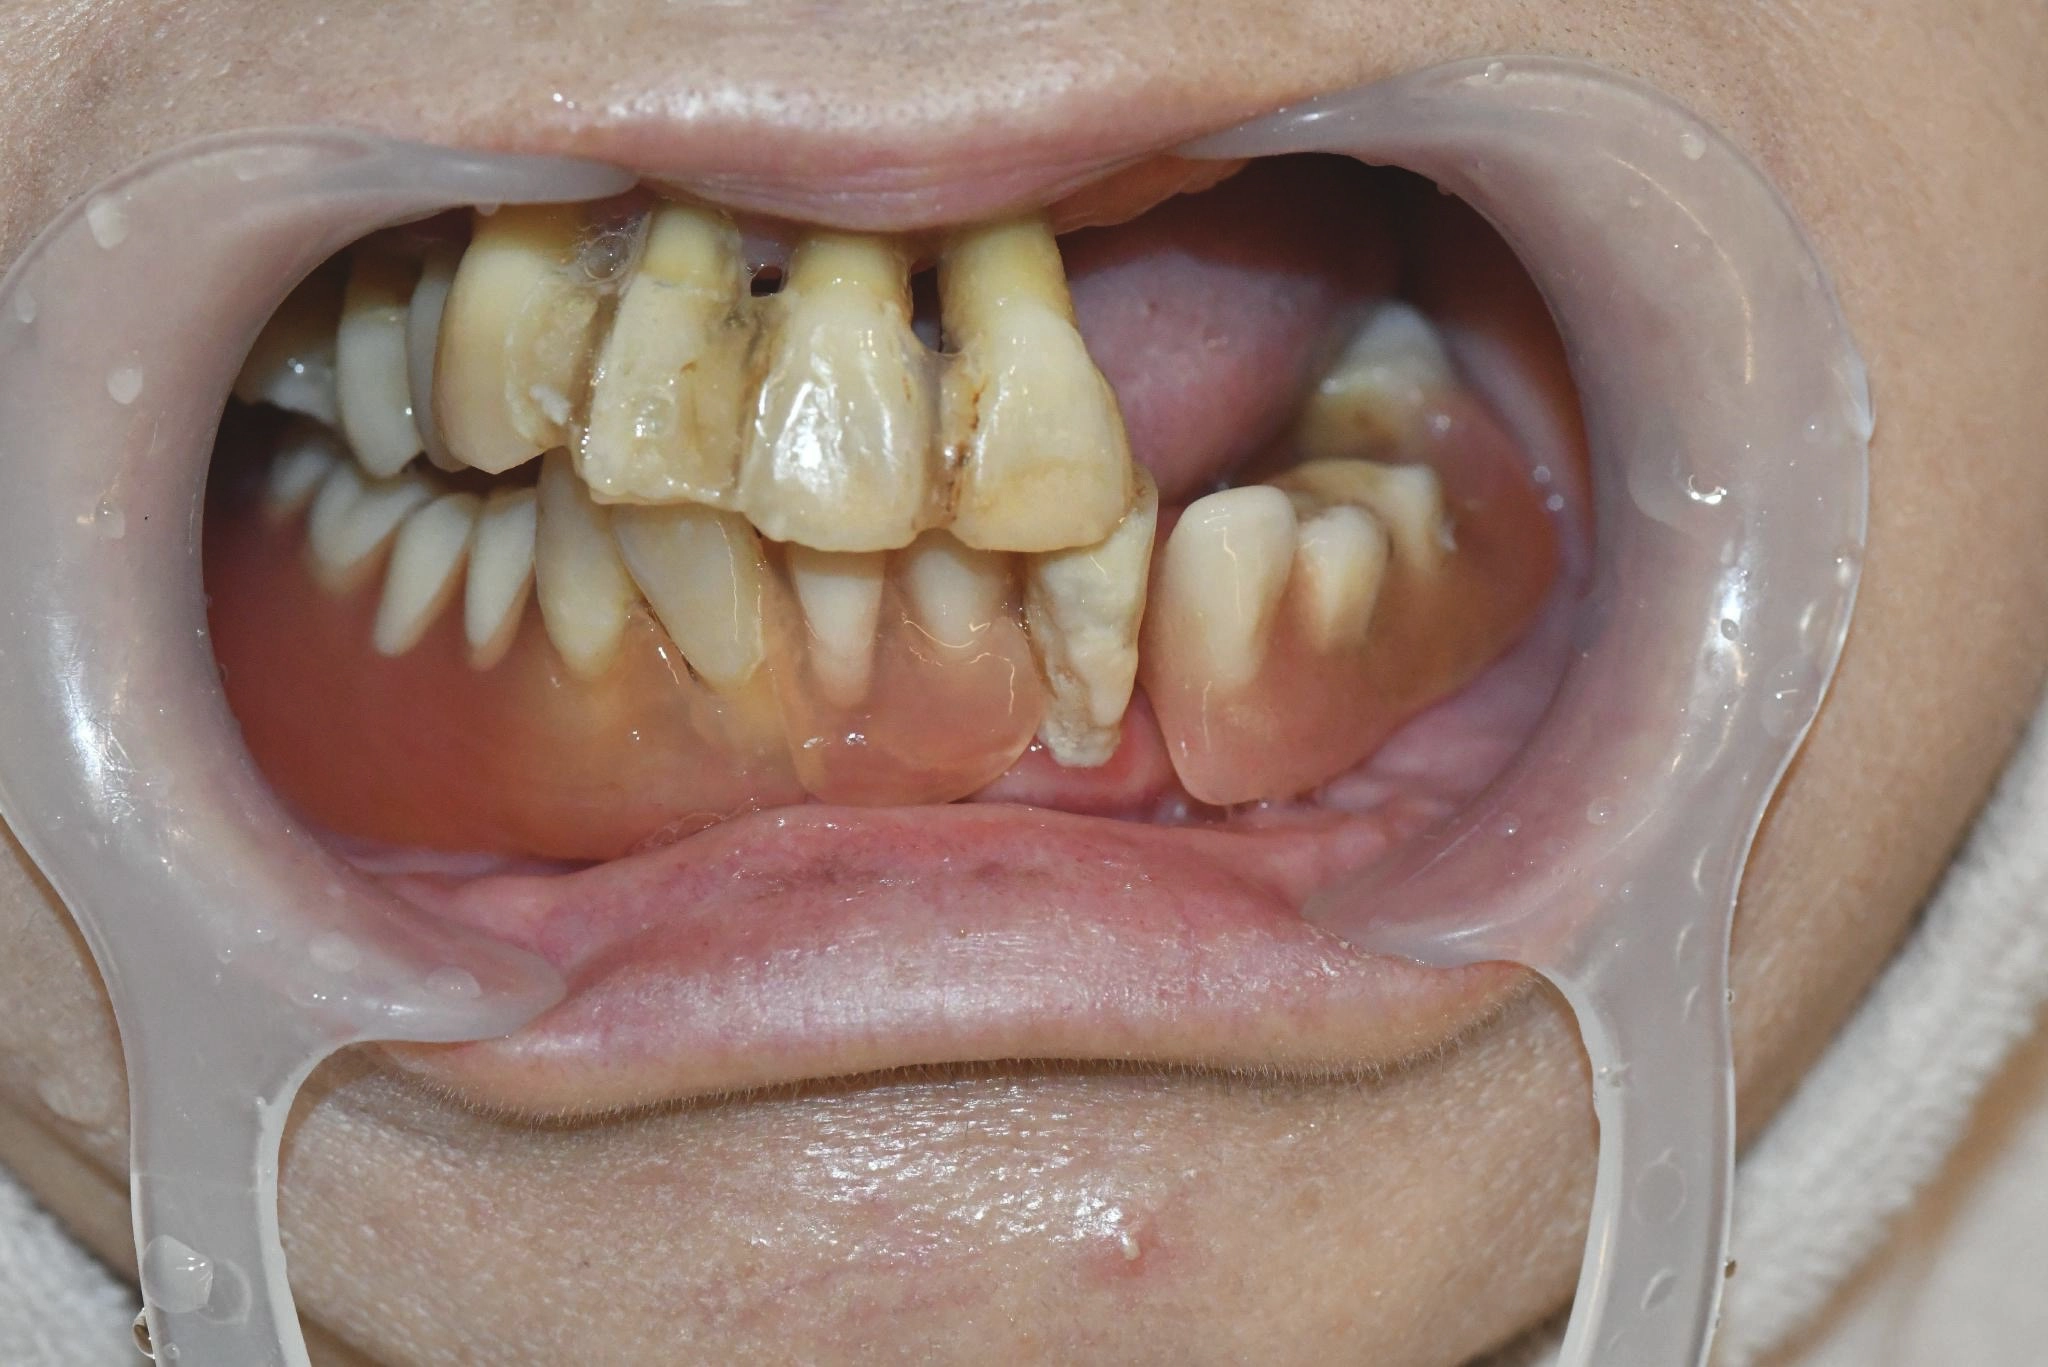

術前

内容 :上下顎オールオン4ザイゴマ2

費用 :5,552,800円

※モニター価格

期間 :半年

リスク:出血・腫れ・痺れ・痛み

食事をしてもうめく噛めないため、食べるたびに不便さを感じていました。見た目も気になり、人前で口元を見せることに抵抗がありました。6年前に他院で作ってもらった入れ歯が合わず、解決しない状況が続いていました。

カウンセリングに行くと、スタッフの方が親切に対応してくれ、オールオン4ザイゴマという治療法について詳しく知ることができました。悩みを根本的に解決したいと思い、手術を決意しました。